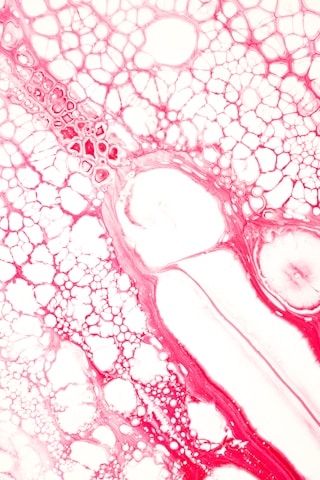

red and white water droplets